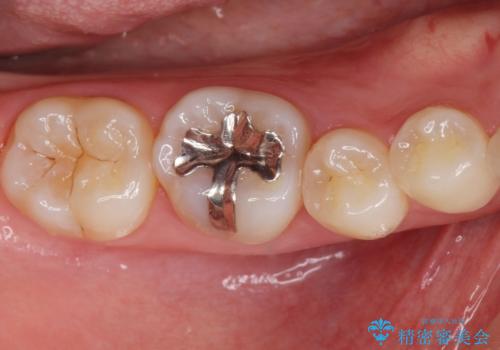

[ 歯肉縁下齲蝕 ] 歯周外科を行った虫歯治療